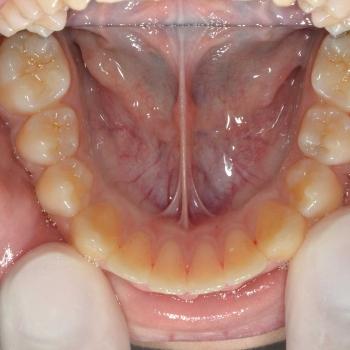

Ákos és édesanyja talán az egyik legjobb korban, 11 évesen kerestek fel a felső fogív túlzott előredőlése miatt. Az első vizsgálat alkalmával, az említett problémán túl, asszimetrikus Angle II-es harapási eltérést diagnosztizáltunk (a bal oldalon 3mm-es, a jobb oldalon 6mm-es eltéréssel)

A kezelési terv nyaki húzású headgear-t, alsó és felső hagyományos fém fogszabályozót, illetve különböző intermaxilláris gumihúzásokat tartalmazott, melyeket Ákos nagy kitartással és utasításszerűen hordott.

Ennek eredményeként sikerült a felső metszőfogakat kellőképpen visszadönteni, illetve korrigálni a harapási eltérést is, ezáltal egy esztétikailag és funkcionálisan is szép eredményt elérni.

A kezelés teljes időtartama: 2.5 év